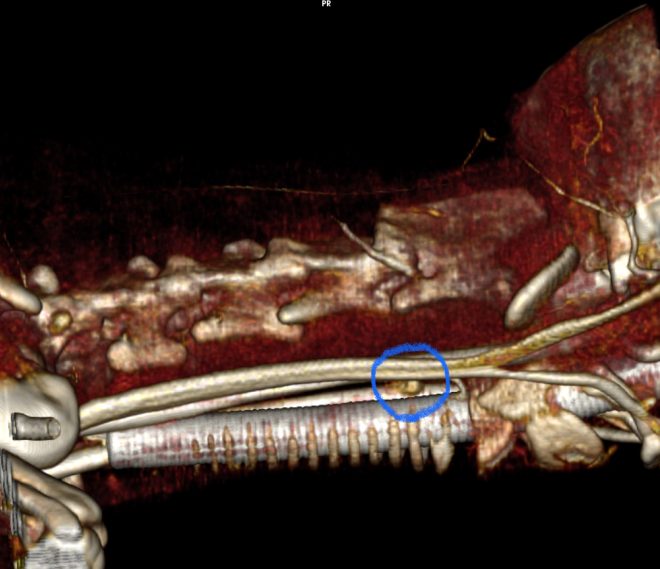

今回治療したワンちゃんの腫瘍は、正常サイズの上限ほどの大きさでした。異所性上皮小体腫瘍が無いことをCT検査で確認し、手術により摘出しました。病理検査は、上皮小体腺癌でした。